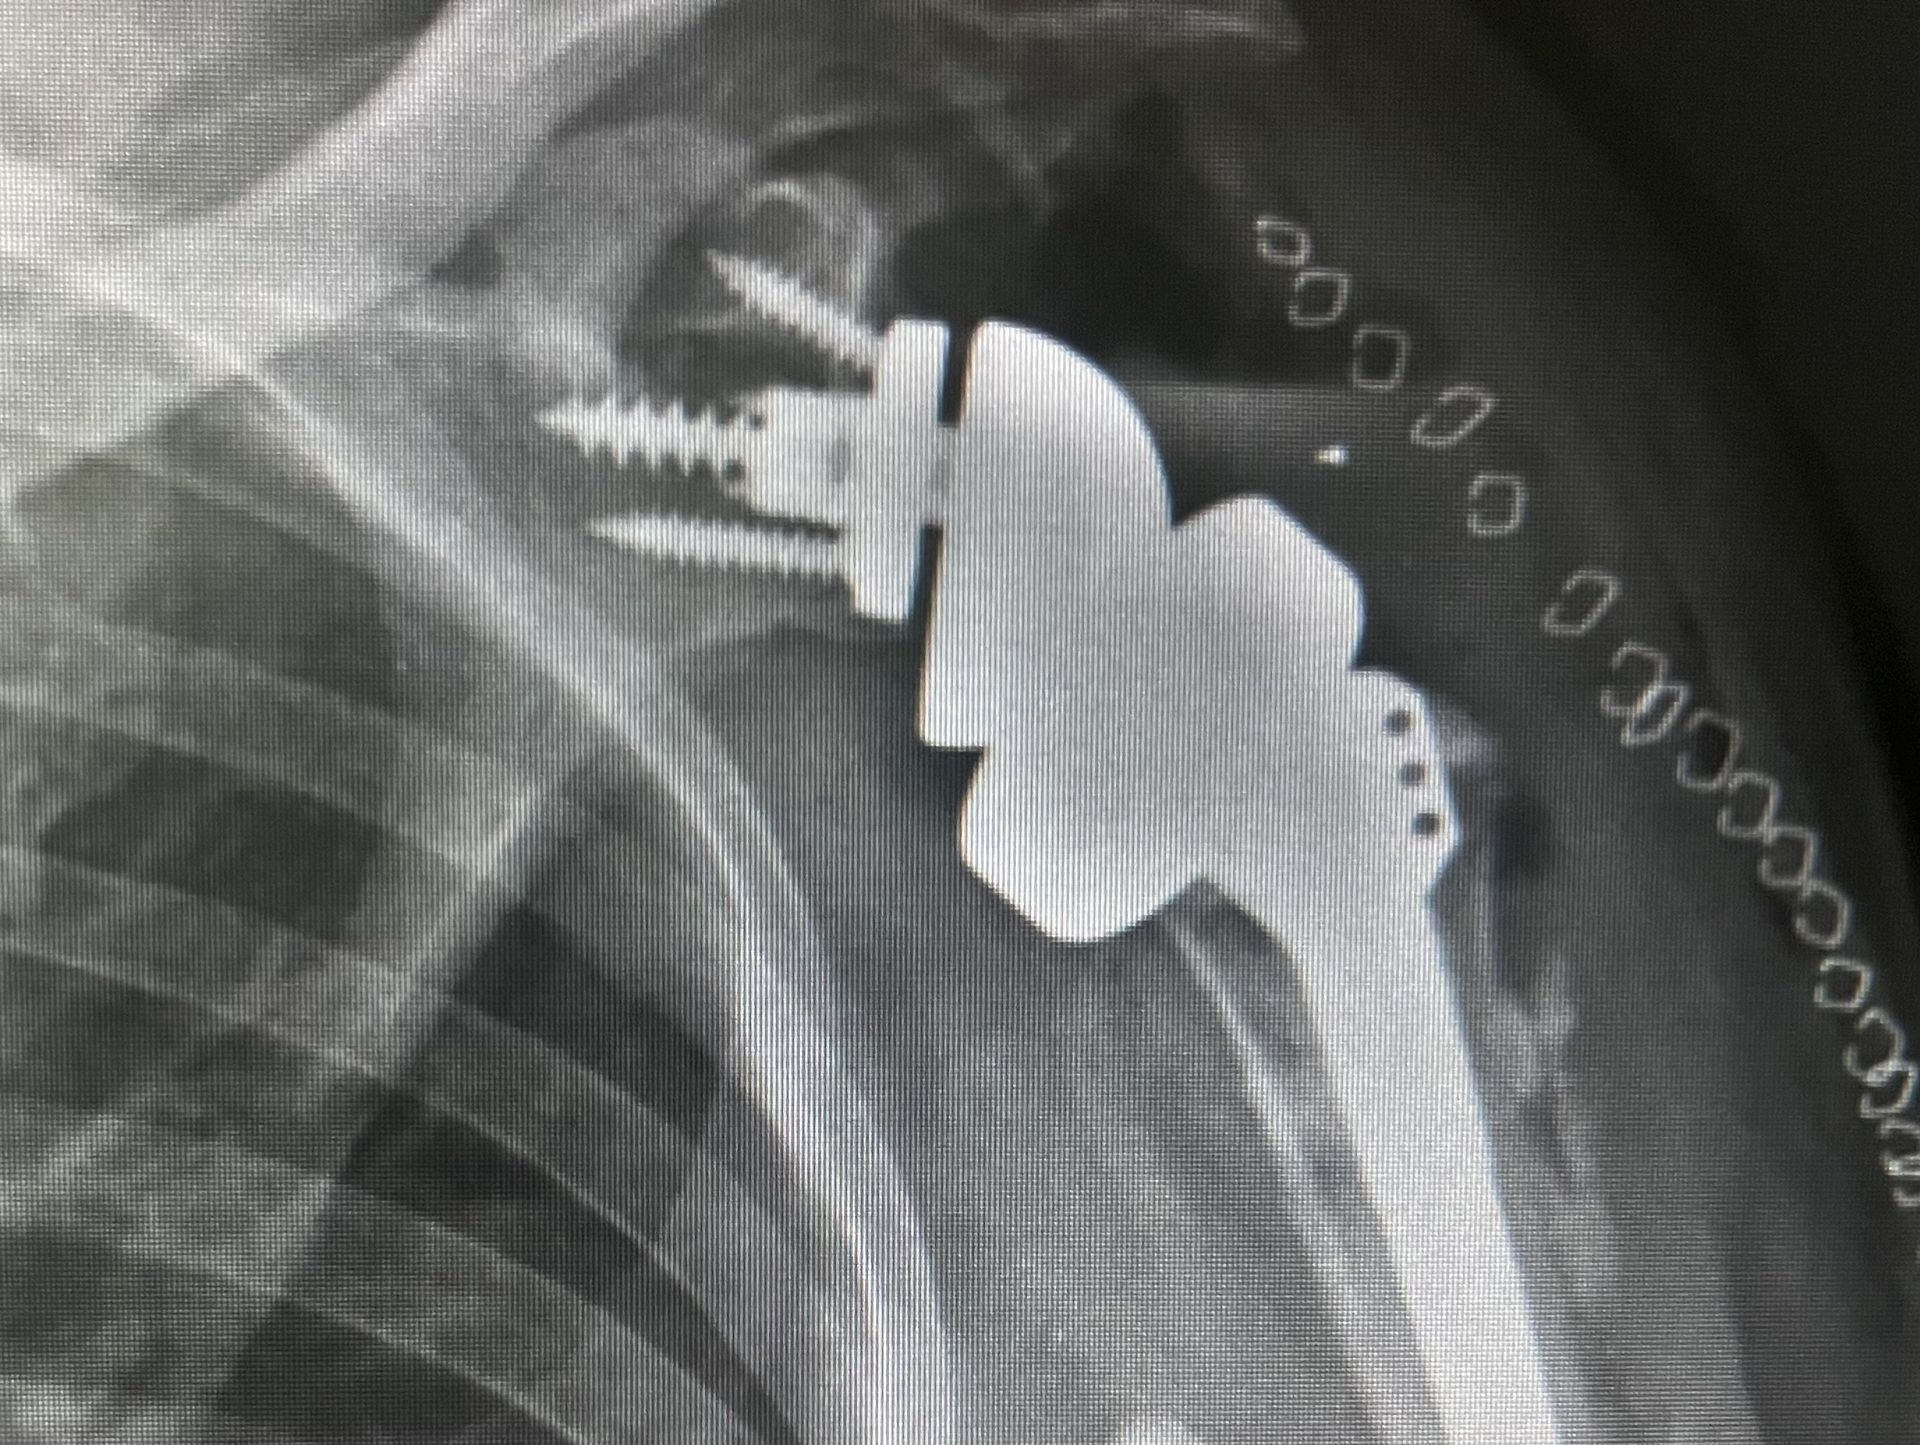

Artrosis Glenohumeral

Esto es la inflamación crónica de la articulación glenohumeral que evoluciona hasta destruir la articulación tanto que esta pierde su función por el desgaste puede ser primaria o posterior a una lesión del manguito rotador, en estos casos el dolor es de fuerte intensidad en casos avanzados, el tratamiento consiste en el reemplazo articular con una prótesis anatómica cuando el manguito rotador esta en buenas condiciones y una prótesis reversacuando el manguito rotador esta comprometido.